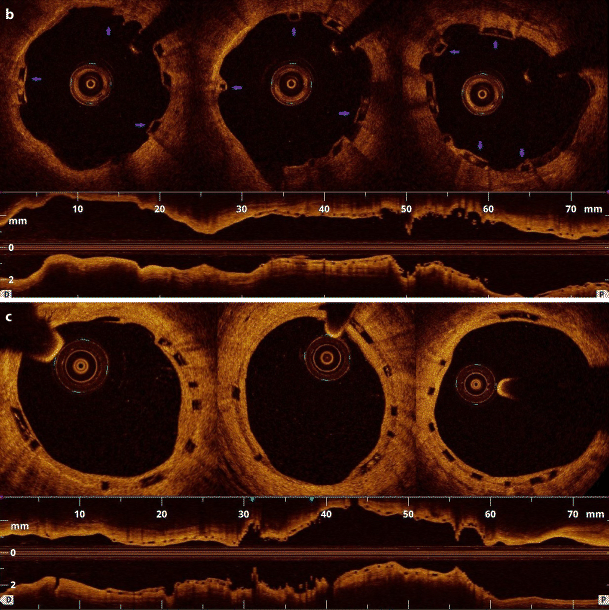

a (Baseline) Optical coherence tomography (OCT) directly after implantation of the bioresorbable scaffold (BVS). Adequate BVS expansion and focally malapposed struts in the distal 3‑mm scaffold segment (white arrow) into right coronary artery. b (1-year follow-up) Uncovered stent struts (blue arrows) at 12 months after the intervention. c (2-year follow-up) 24-month OCT revealed complete coverage of all struts with a homogeneous, bright neointimal layer and resolved malapposition in the distal segment

A 67-year-old male underwent primary percutaneous coronary intervention for inferior ST-segment elevation myocardial infarction. The patient further underwent aspiration thrombectomy, abciximab infusion and predilatation with subsequent implantation of two bioresorbable scaffolds followed by post-dilatation with a non-compliant balloon in the right coronary artery. The optical coherence tomography (OCT) confirmed good scaffold expansion, with focally malapposed struts in the distal 3‑mm scaffold segment. Twelve months later, at the prespecified evaluation, the vessel was patent without evidence of restenosis or thrombus, however, the OCT revealed a substantial rate of uncovered struts (8.5%). Interestingly, all struts were covered by neointima at the 24-month examination. Based on these findings, prolonged dual antiplatelet therapy was ceased after two years from the index procedure. Discontinuation of P2Y12 antagonist at 12 months potentially could have led to late scaffold thrombosis in our patient with initially impaired endothelial healing response (see Fig. 1).